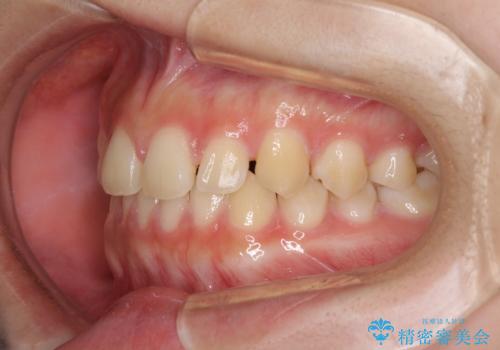

前歯のすきっ歯を治したい インビザラインによる矯正治療

- 上顎前歯の隙間を気にして来院された患者様です。

目立たない装置を希望とのことで、インビザラインを用いて矯正治療を行うこととしました。

一度インビザラインのマウスピースセットをお渡しすると1年以上来院されず、マウスピースを破損したり紛失したりすると来院されるというのんびりとしたペースで治療を行ったため、4年間という長期にわたる治療となりました。

最終的には隙間は全て閉じ、綺麗な仕上がりとなりました。